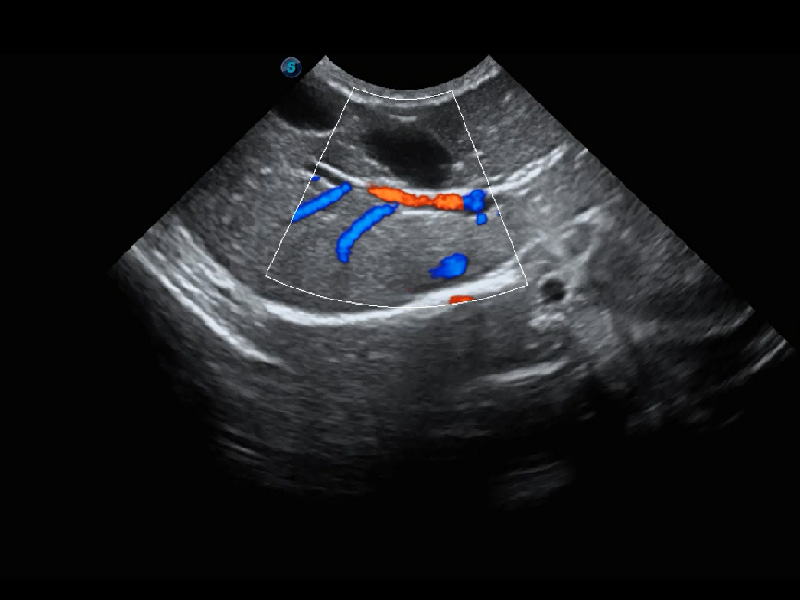

兽用彩色多普勒超声诊断系统

ProPet 60 作为一款高端台式动物超声设备,为动物医生的日常诊断提供了一系列贴合动物临床需求、解决临床实际问题的高级成像功能。凭借全系列高清探头,满足医生对腹部、心脏、生殖、浅表、肌骨等成像的所有需求,切实帮助您提升检查效率,提高诊断信心。